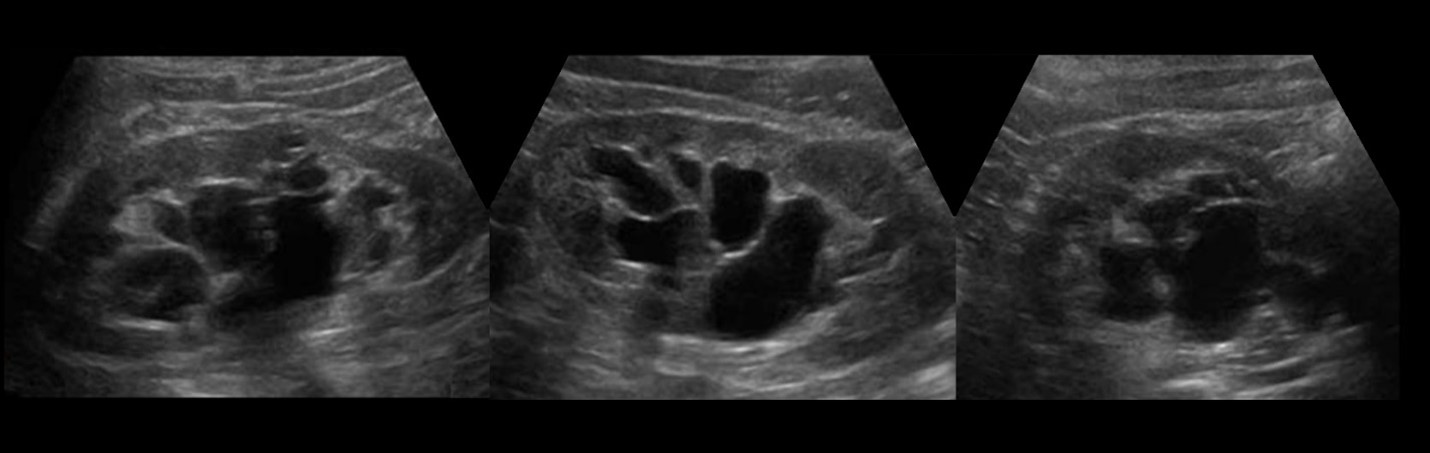

سونوگرافی زنان و زایمان از سال 1950 یک ابزار تشخیصی مفید است که به عنوان روشی ایمن، غیرتهاجمی، دقیق و مقرون به صرفه برای نظارت بر رشد کودک در حال رشد شناخته می شود. امروزه از اسکنرها برای نمایش تصویر پیوسته از جنین در حال حرکت بر روی صفحه نمایش استفاده می شود تا اطلاعات مهم پزشکی توسط متخصصان قابل تفسیر باشد. بنابراین، تفسیر سونوگرافی کودک شما بهتر است توسط متخصصان تشخیص داده شود.

برای گزارش سونوگرافی می توانید از خدمات تفسیر از راه دور سایت گزارش آنلاین استفاده کنید. در سایت گزارش آنلاین تفسیر سونوگرافی و جواب آزمایش شما توسط متخصصان این حوزه بررسی و در کمترین زمان ممکن یک گزارش جامع به شما ارائه می شود. در طول تفسیر و مشاوره پزشکی هرگونه سوال یا ابهامی که داشته باشید توسط متخصص پاسخ داده خواهد شد. سونوگرافی که بین هفتههای 18 تا 20 گرفته میشود، اولین تأییدیه جنسیت کودک شما است به این دلیل استفاده از تفسیر مجدد یک پزشک متخصص می تواند شما را از نتایج بدست آمده مطمئن کند. این مقاله به شما کمک میکند تا بدانید در تصاویر دقیقاً به دنبال چه چیزی هستید.

در تفسیر گزارش سونوگرافی تفاوت بین رنگ ها را درک کنید. سونوگرافی یا اولتراسوند یک عکس سیاه و سفید است که در ابتدا ممکن است کمی گیج کننده باشد. وقتی که به این نکات توجه کنید، مشاهده جزئیات کودک شما آسان تر می شود. هرچه بافت جامد و محکم تر باشد، تصویر واضحتر است، به عنوان مثال، استخوانها خاکستری روشن یا سفید رنگ هستند.